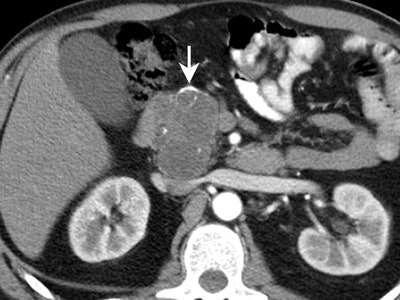

![]() |

| Serous cystadenoma with classic central, stellate calcification. All images courtesy of Dr. Brendan Visser. |